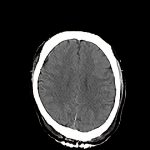

髄膜腫

断層撮影

手術前1

手術後

No.’12_148 手術前1

No.’12_148 手術後